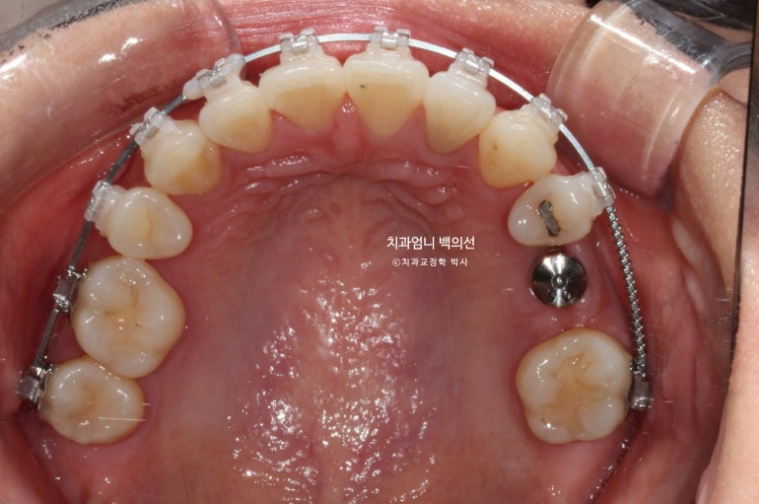

24.08

윗니 중심선이 코와 인중 및 얼굴과 맞아진 것은 치료시작 1년 후 입니다.

이때부터 아래 치아에도 클리피씨 장치를 붙이고 배열을 시작했습니다.

치료시작 1년 3개월차, 결손된 큰어금니 공간이 충분히 확보되어 드디어 임플란트를 식립했습니다.

24.11